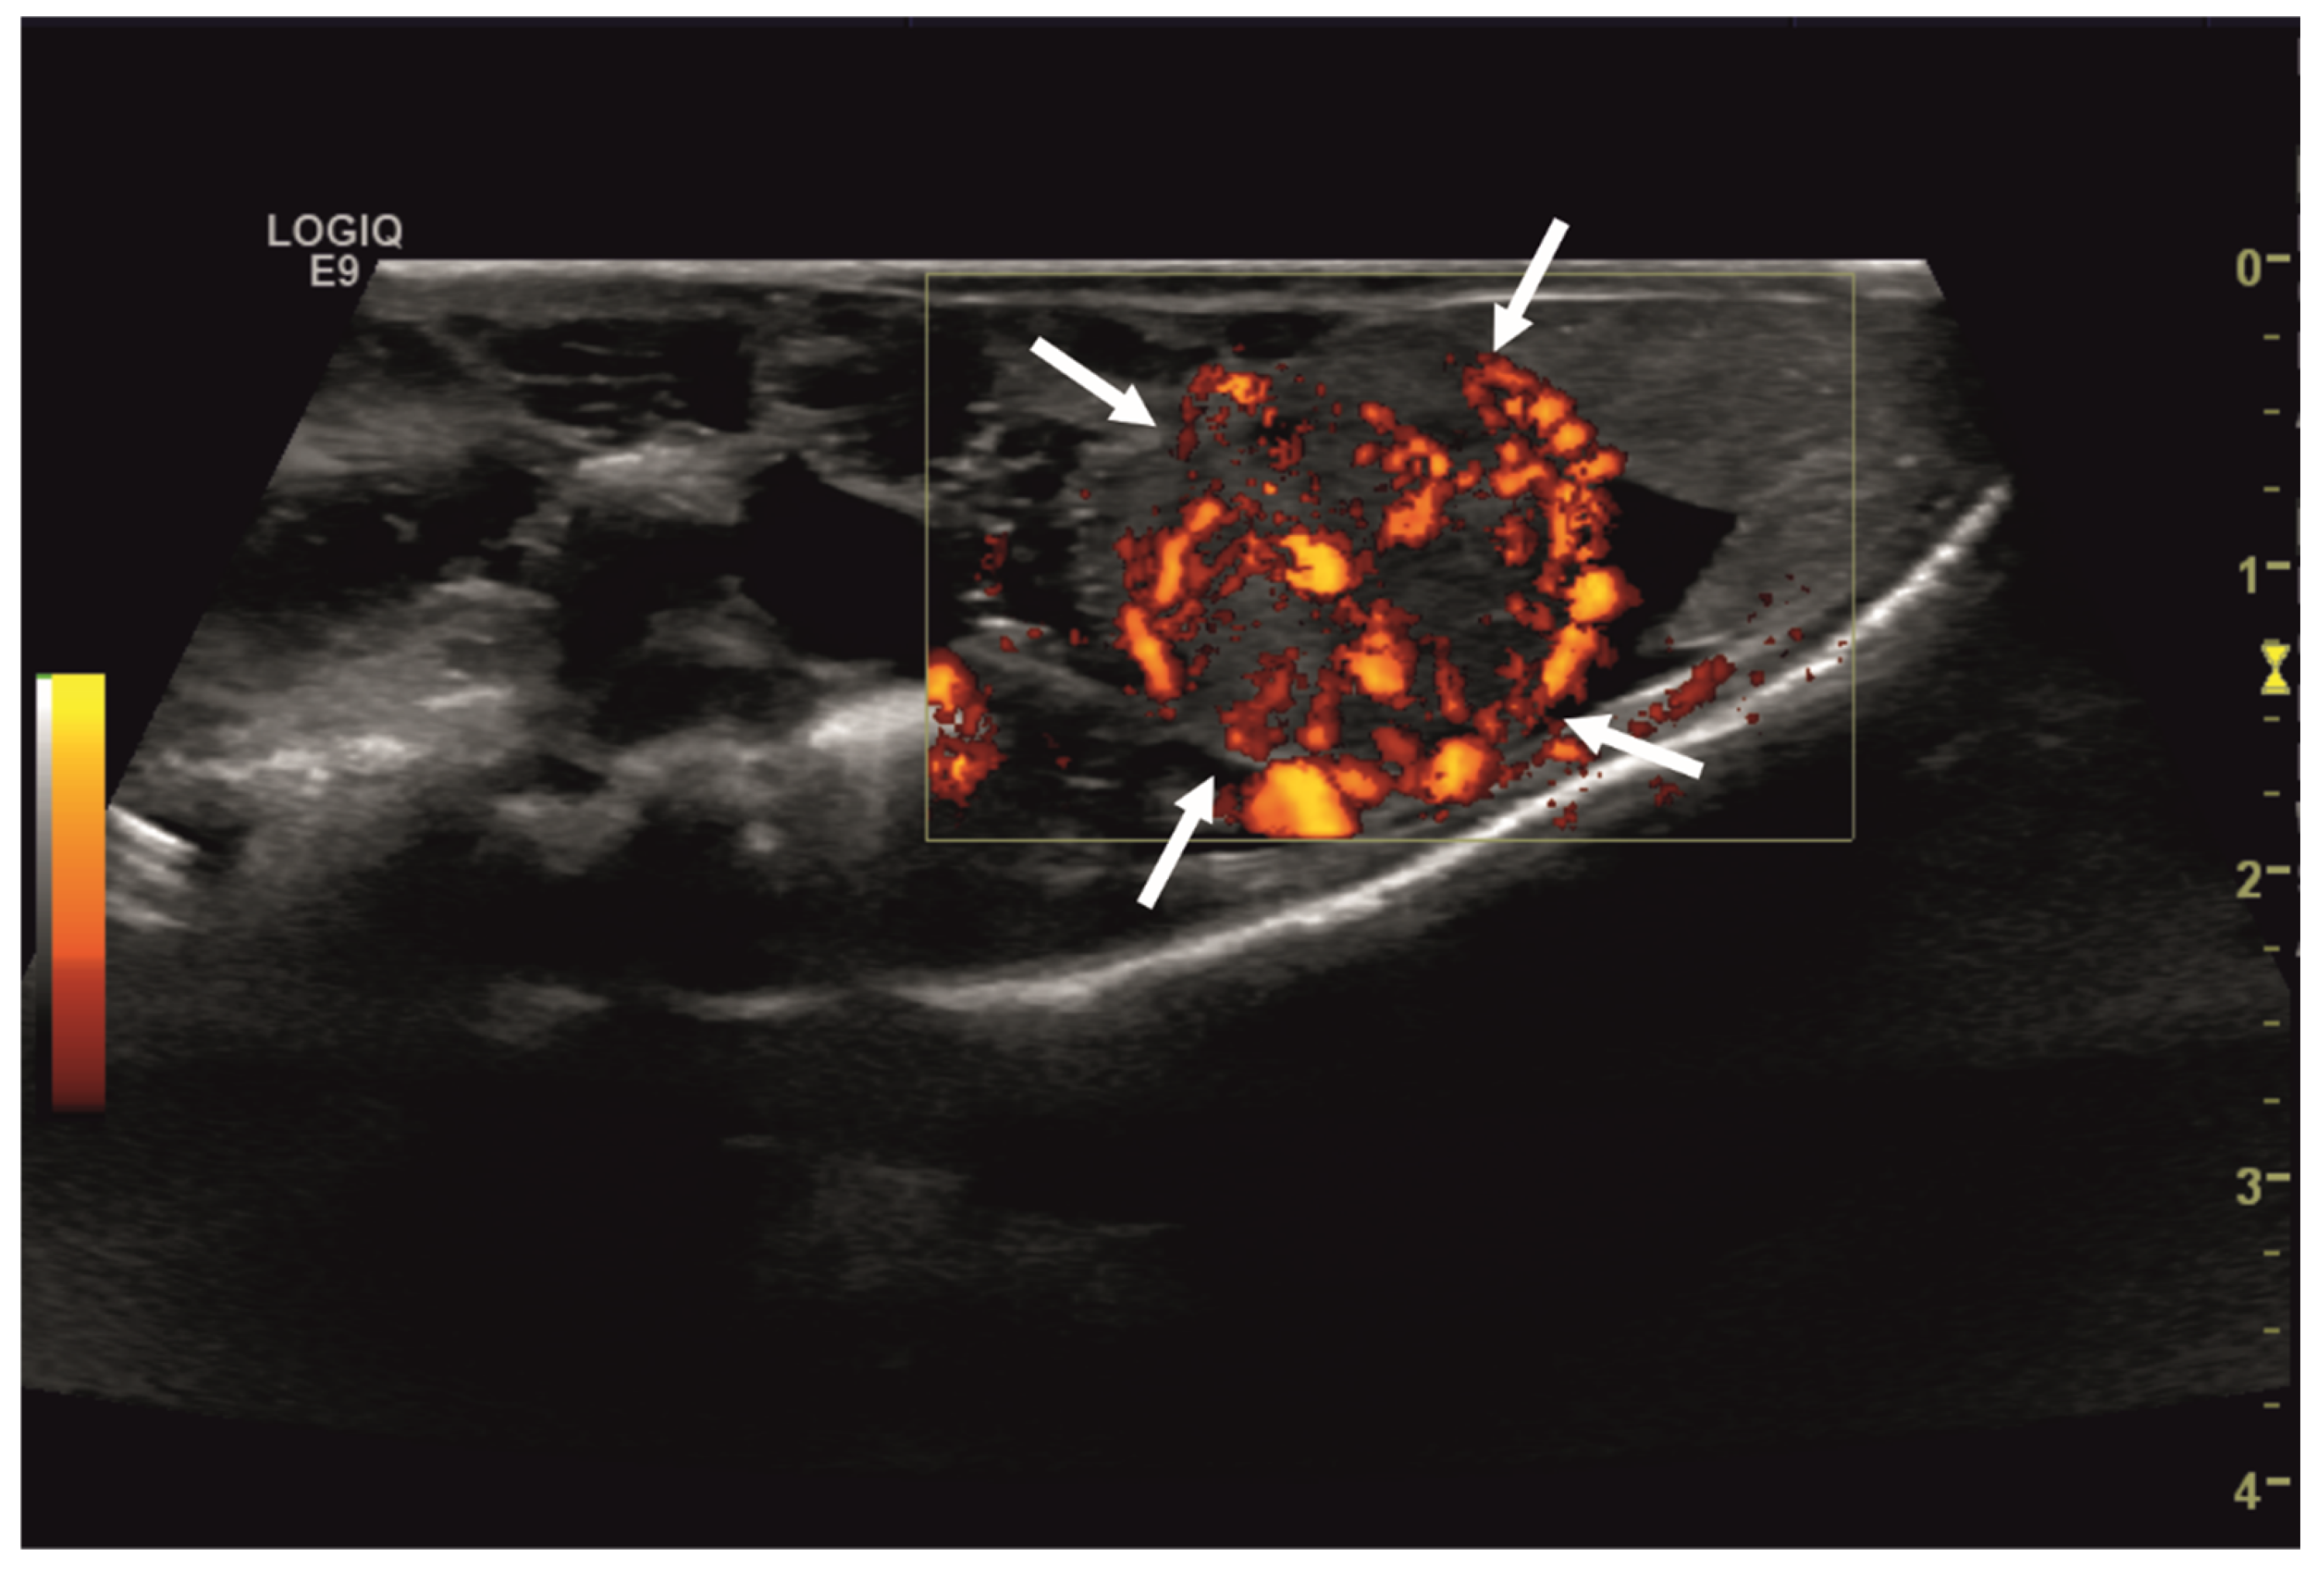

Initial diagnostic methods included parasitological fecal examination, radiography, and ultrasonography. The animal owner declined a blood examination due to financial restrictions. Microscopic fecal examination at 100× magnification revealed a high infestation of oxyurids (>20 eggs per field of view) and a low-grade flagellate infestation. Under manual restraint, dorsoventral and horizontal beam lateral radiographic projections were performed (Figure 1; digital X-ray; detector system: Fujifilm Console Advance DR-ID 300 CL, Fujifilm Europe GmbH, Düsseldorf, Germany; tube system: Gierth X-ray International GmbH, Riesa, Germany; film focus distance FFD 60 cm, 50 kV, 5 mAs). The lateral radiograph was insufficient for any evaluation due to a technical issue. On the dorsoventral view, the medial right coelom was filled with soft-tissue material and hypodense areas (moderately filled gastrointestinal tract and gastrointestinal gas). Mineral opacities were visible in the left coelom, indicating deposits of foreign material (sand or similar anorganic substrate) in the large intestine. Both lung fields were visible on the dorsoventral radiograph, though superimpositions with the gastrointestinal tract did not allow a clear evaluation of the entire lung field size. No distinct intracoelomic lesion was determinable upon radiography. Ultrasonographic examination under manual restraint and in dorsal recumbency (Micro curved array transducer, 5–9 MHz; Vivid 7 Dimension; GE Healthcare GmbH, Solingen, Germany) with transverse and longitudinal views from the ventral coupling site showed an approximately 2 × 1.5 cm round-shaped, intracoelomic mass located in the middle third of the medial right coelom. The structure was surrounded by intestinal and fat body tissue (Figure 2). However, the mass showed good vascularization, and demarcation to surrounding tissue was clearly feasible (Figure 3). No other abnormalities of coelomic organs were visualized during the ultrasound examination.

Figure 3. Transverse ultrasonographic image of the medial right coelom in a bearded dragon acquired with a 5 to 9 MHz micro curved array transducer and Color Doppler evaluation (penetration depth 2 cm; frequency 15 MHz). Note the distinct vascularization of the round-shaped intracoelomic mass (arrows). Additionally, gastrointestinal tract (medial, here: to the left of the mass) and fat body (lateral, here: to the right of the mass) are visible and closely related to the mass.